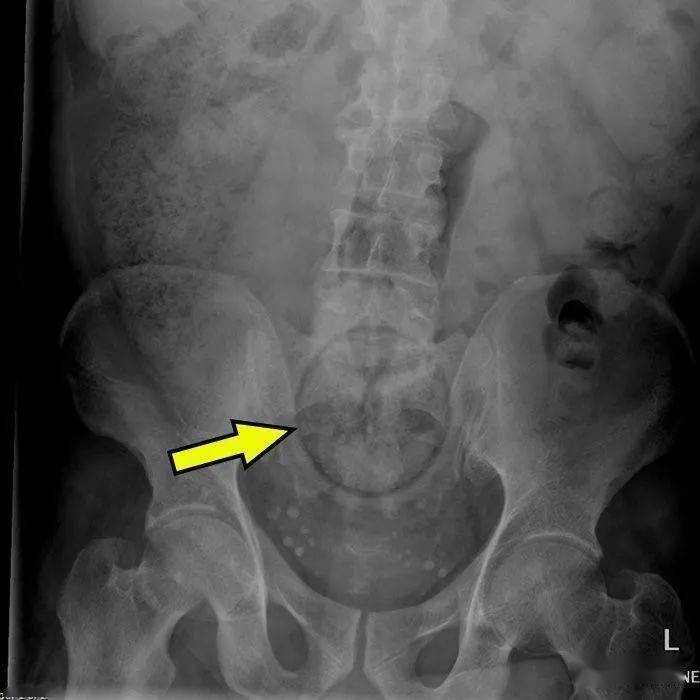

▷橘子谁说水果一定让你身体好的?(狗头.jpg